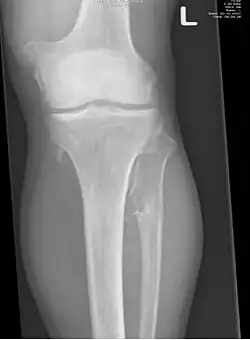

Mnogie kostniakochrzęstniaki (ang. multiple osteochondromas, hereditary multiple exostoses, HME, multiple hereditary exostoses, MHE, EXT, diaphyseal aclasis (multiple hereditary) osteochondromatosis, multiple cartilaginous exostoses) – uwarunkowana genetycznie choroba polegająca na wrodzonej predyspozycji do kostniakochrzęstniaków kości długich.

Osteochondromata pojawiają się i powiększają w pierwszej dekadzie życia, ich wzrost ulega zahamowaniu wraz z okresem dojrzewania. Zmiany są uszypułowane lub nie i bardzo zmiennej wielkości. Przeciętna liczba kostniakochrzęstniaków wynosi 15–18; może być ich mniej lub więcej, w zależności od rodziny i od pacjenta. Większość jest bezobjawowa. Kości, z których wychodzą zmiany, to kości długie, przede wszystkim kość udowa i kości podudzia. Kości twarzoczaszki nie są miejscem gdzie osteochondromata mogą się lokalizować. Objawy to ból i deformacje stawów, zwłaszcza w przypadku zmian zlokalizowanych w okolicy łokcia. Najistotniejszym powikłaniem jest złośliwienie zmian w kierunku chrzęstniakomięsaka, mające miejsce w 0,5–5% przypadków.

Rozpoznanie opiera się na badaniu klinicznym i radiologicznym oraz, o ile to możliwe, na histopatologicznej ocenie wycinka guza. Jeśli znane jest miejsce mutacji, technicznie możliwe jest zdiagnozowanie prenatalne choroby,